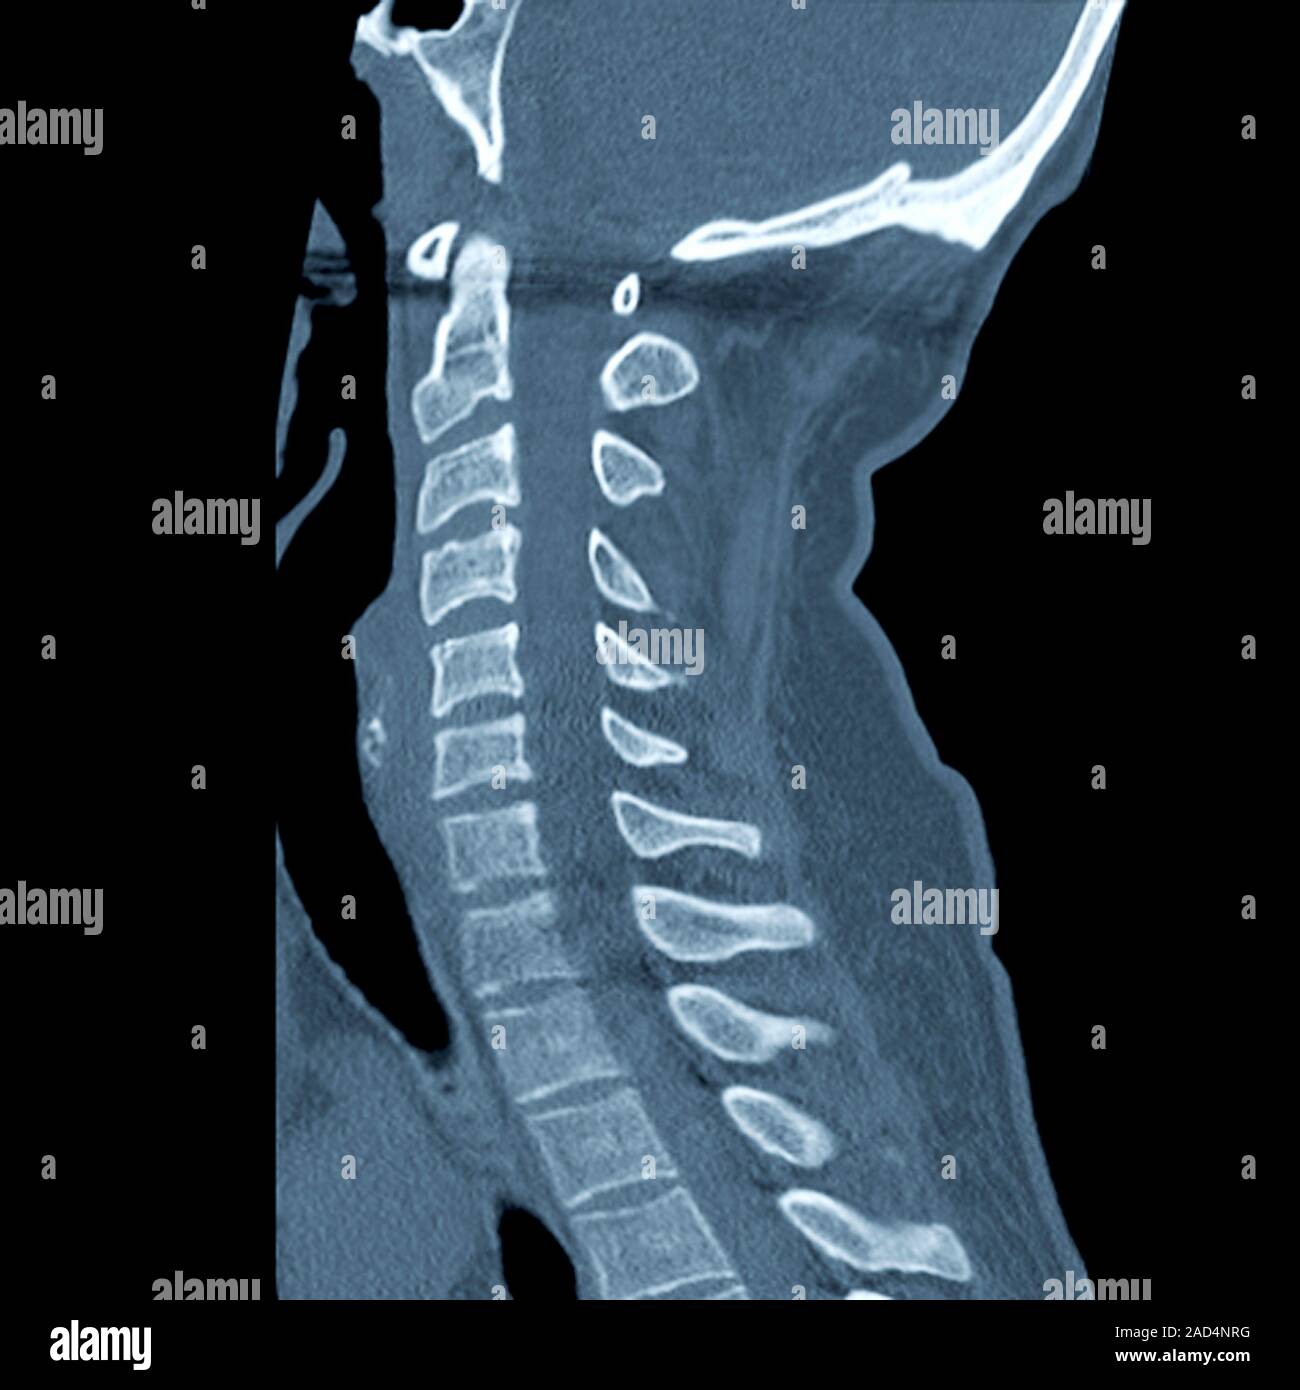

Slipped disc. Coloured computed tomography (CT) scan of a section Slipped Disk In Cervical Spine Rarely, the pain, tingling, numbness, and/or weakness can go into both arms or lower in the body if the spinal cord is affected. common causes of cervical herniated disc include: — a herniated disk occurs when some of the softer material inside the disk pushes out through a crack in the tougher. — a herniated or slipped. Slipped Disk In Cervical Spine.

Slipped disc. Computed tomography (CT) scan of a section through the Slipped Disk In Cervical Spine If the disk is pressing on a nerve root, other. Rarely, the pain, tingling, numbness, and/or weakness can go into both arms or lower in the body if the spinal cord is affected. — a herniated cervical disk is one of the most common causes of neck pain. A direct impact on the spine can cause a disc to. Slipped Disk In Cervical Spine.